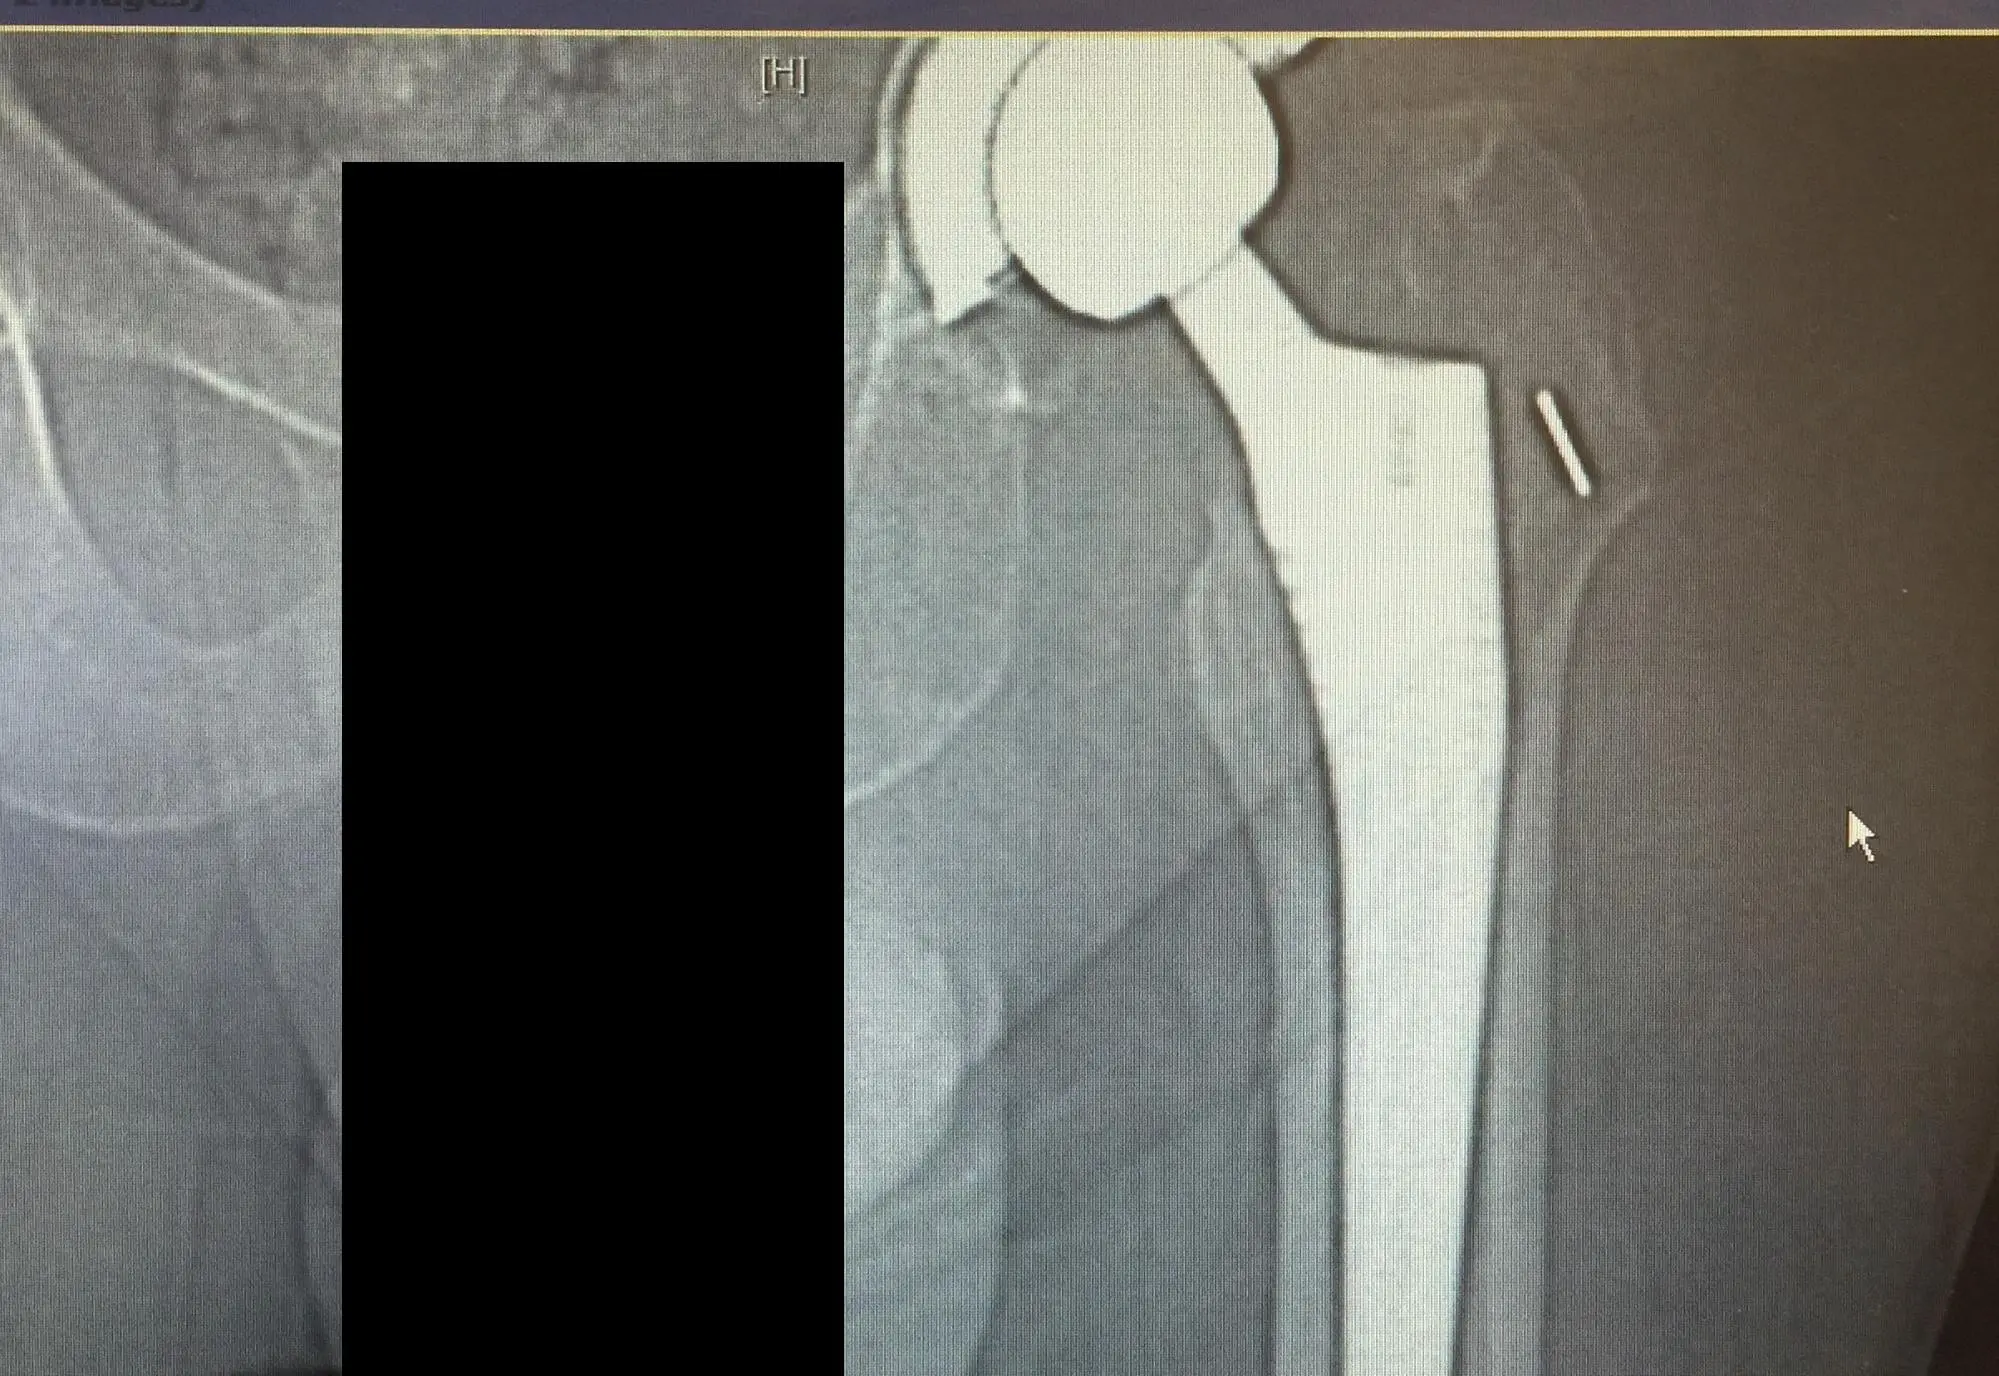

CT scan and X-ray of the left hip revealed a nondisplaced periprosthetic fracture of the proximal femur anteromedially with subsidence of the stem.

Preoperative diagnosis: Left hip periprosthetic fracture with a loose stem and with subsidence.